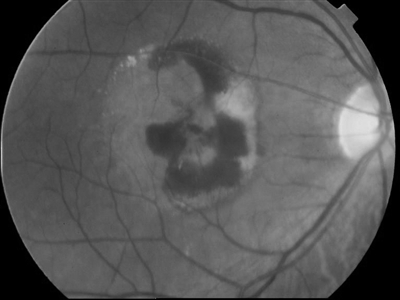

湿性老年性黄斑变性黄斑区出血及渗出

说到老年性黄斑变性先要了解黄斑是什么。它既不是绿色树叶生病而出现的黄色斑点,也不是人们脸上长出的那些令人不快的色斑。其实黄斑不是斑,它是我们眼睛看东西最关键的部位,是视网膜上是一个正常结构。如果把照相机比作眼睛,视网膜就是这个照相机的胶片,而黄斑就是视网膜胶片上最中心、最重要的部分。离开了这部分,无论你有再昂贵的相机,再好的镜头,都拍不出好的照片来。黄斑也像容颜一样会变老,在黄斑发生老化的时候,首先会长出一些类似老年斑样的东西,叫作玻璃膜疣。出现了这个玻璃膜疣,我们就称它为发生了干性老年性黄斑变性。而在一些特殊情况下,眼底黄斑区还会长出一些有问题的新生血管,这些新生血管会发生出血和渗漏,类似于水管发生漏水,所以又称之为为湿性老年性黄斑变性。视力因此也会经历由视物模糊、中心小暗点出现、直到中心巨大暗点出现的变化过程。